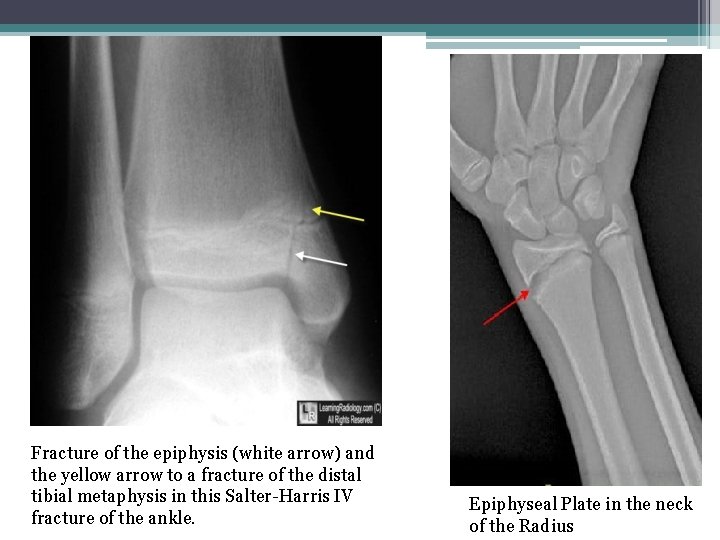

• 8 -Epiphyseal Plate Fracture: It is a form of child bone fracture that involves the epiphyseal plate or growth plate.

Fracture of the epiphysis (white arrow) and the yellow arrow to a fracture of the distal tibial metaphysis in this Salter-Harris IV fracture of the ankle. Epiphyseal Plate in the neck of the Radius